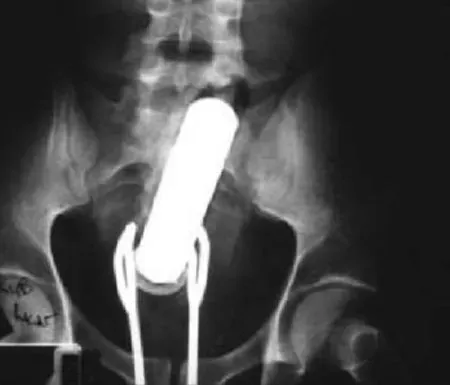

(2)진동기와 샐러드 집게:이 남성은 항문에 진동기가 끼어버리는 사고가 발생한다. 그래서 샐러드 집게로 빼내려하지만 불행히 그 집게도 끼어버렸다.